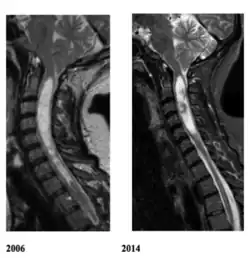

La siringomielia es un trastorno en el cual se forma un quiste dentro de la médula espinal. Este quiste se conoce como siringe o syrinx. Con el tiempo, el syrinx se expande y alarga, destruyendo el centro de la médula espinal. Puesto que la médula espinal conecta el cerebro con los nervios de las extremidades, este daño causa dolores, debilidad y rigidez en la espalda, los hombros, los brazos o las piernas. Otros síntomas pueden incluir dolores de cabeza (cefalea) y pérdida de la capacidad de sentir calor o frío extremos, especialmente en las manos. Cada paciente tiene una combinación distinta de síntomas.

La mayoría de los síntomas se deben a la lesión irreversible del tejido nervioso, y este no es capaz de reemplazarlo; sin embargo, parece ser que en la siringomielia idiopática la sección del filum terminale detiene la enfermedad.[4] El quiste resultado de la necrosis celular queda igual, pero puede desaparecer cuando espontáneamente se abre el espacio que rodea la médula espinal o lo hace hacia el centro de ella donde existe un conducto, el conducto ependimario, que comunica el centro de la médula con las cavidades cerebrales.